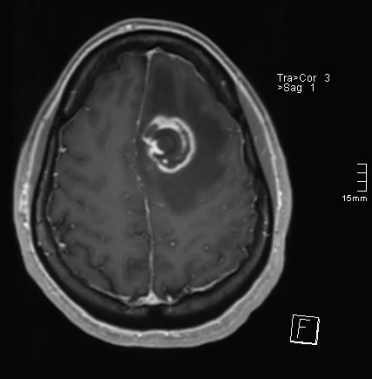

Helena, mulher cis, 56 anos, é levada ao pronto atendimento devido a episódio de fraqueza súbita em membro inferior direito, que dificultou a marcha, há cerca de 6 horas, evoluindo com crises convulsivas. O acompanhante informa que a paciente é acompanhada em UBS por hipertensão arterial, dislipidemia e diabetes mellitus, com antecedente de AVE isquêmico há 8 anos, do qual se recuperou sem déficits. Ao exame neurológico, apresenta Glasgow 14, déficit neurológico focal restrito a membro inferior direito, preservando força nos demais membros, sem alteração de fala, com reflexos pupilares normais, sem desvio de rima labial e ausência de sinais de irritação meníngea. Sinais vitais estáveis, exceto temperatura axilar de 37,7°C. Teste rápido para HIV na admissão foi reagente. Realizada RM de crânio abaixo.

O diagnóstico mais provável para este caso é